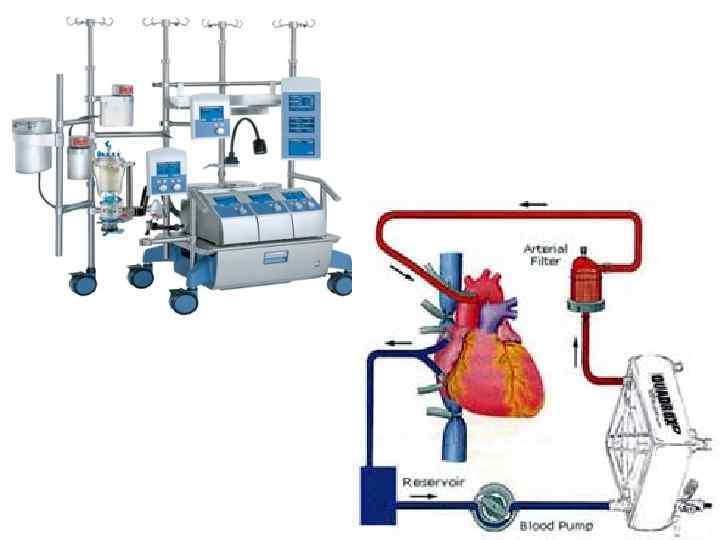

Жүректі тоқтату арқылы Жүректі тоқтатпай Жасанды қан айналдыру аппараты қажет емес Жасанды қан айналдыру аппараты қажет Артықшылықтары: Қан элементтері зақымдалмайды Операция уақыты қысқарады Опреациядан кейінге ерте реабилитация

Жүректі тоқтату арқылы Жүректі тоқтатпай Жасанды қан айналдыру аппараты қажет емес Жасанды қан айналдыру аппараты қажет Артықшылықтары: Қан элементтері зақымдалмайды Операция уақыты қысқарады Опреациядан кейінге ерте реабилитация

Акш этаптары 1. Ортаңғы стернотомия ар-ы жүрекке доступ 2. Басқа бригада жүргізетін аутотрансплантантты алу 3. Аортаның жоғарылаған бөлігін ж/е, қуысты веналарды канюляциялап жасанды қан айналдыру аппаратына қосу 4. Жүректі кардиоплегиялық тоқтатау ж/е аортаның жоғарылаған бөлігін қысу 5. Тәждік артериямен дисталды анастомоздарды байланыстыру 6. Аортаның жоғарылаған бөлігінен зажимді алу 7. Ауалық эмболияның профилактикасы 8. Жүрек қызметін қалпына келтіру 9. Проксималды анастомоздар салу 10. Жасанды қан айналдыру аппартанын шығару 11. Деканюляция 12. Перикарды дренждау ж/е стернотомиялық кескінді тігу

Акш этаптары 1. Ортаңғы стернотомия ар-ы жүрекке доступ 2. Басқа бригада жүргізетін аутотрансплантантты алу 3. Аортаның жоғарылаған бөлігін ж/е, қуысты веналарды канюляциялап жасанды қан айналдыру аппаратына қосу 4. Жүректі кардиоплегиялық тоқтатау ж/е аортаның жоғарылаған бөлігін қысу 5. Тәждік артериямен дисталды анастомоздарды байланыстыру 6. Аортаның жоғарылаған бөлігінен зажимді алу 7. Ауалық эмболияның профилактикасы 8. Жүрек қызметін қалпына келтіру 9. Проксималды анастомоздар салу 10. Жасанды қан айналдыру аппартанын шығару 11. Деканюляция 12. Перикарды дренждау ж/е стернотомиялық кескінді тігу